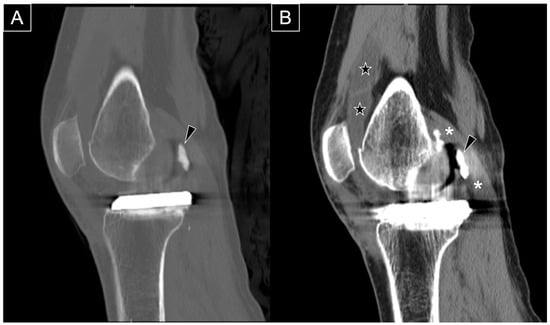

Figure 5.

Sagittal computed tomography (CT) scans in the bone window (A) and soft tissue window (B) demonstrate extruded cement (black arrowhead) positioned posterior to the metallic femoral component. The CT scans confirm that both the femoral and tibial metallic components are securely fixed to the bone. The extruded cement impinges on the medial head of the gastrocnemius muscle (asterisk), and significant knee effusion is evident (star).